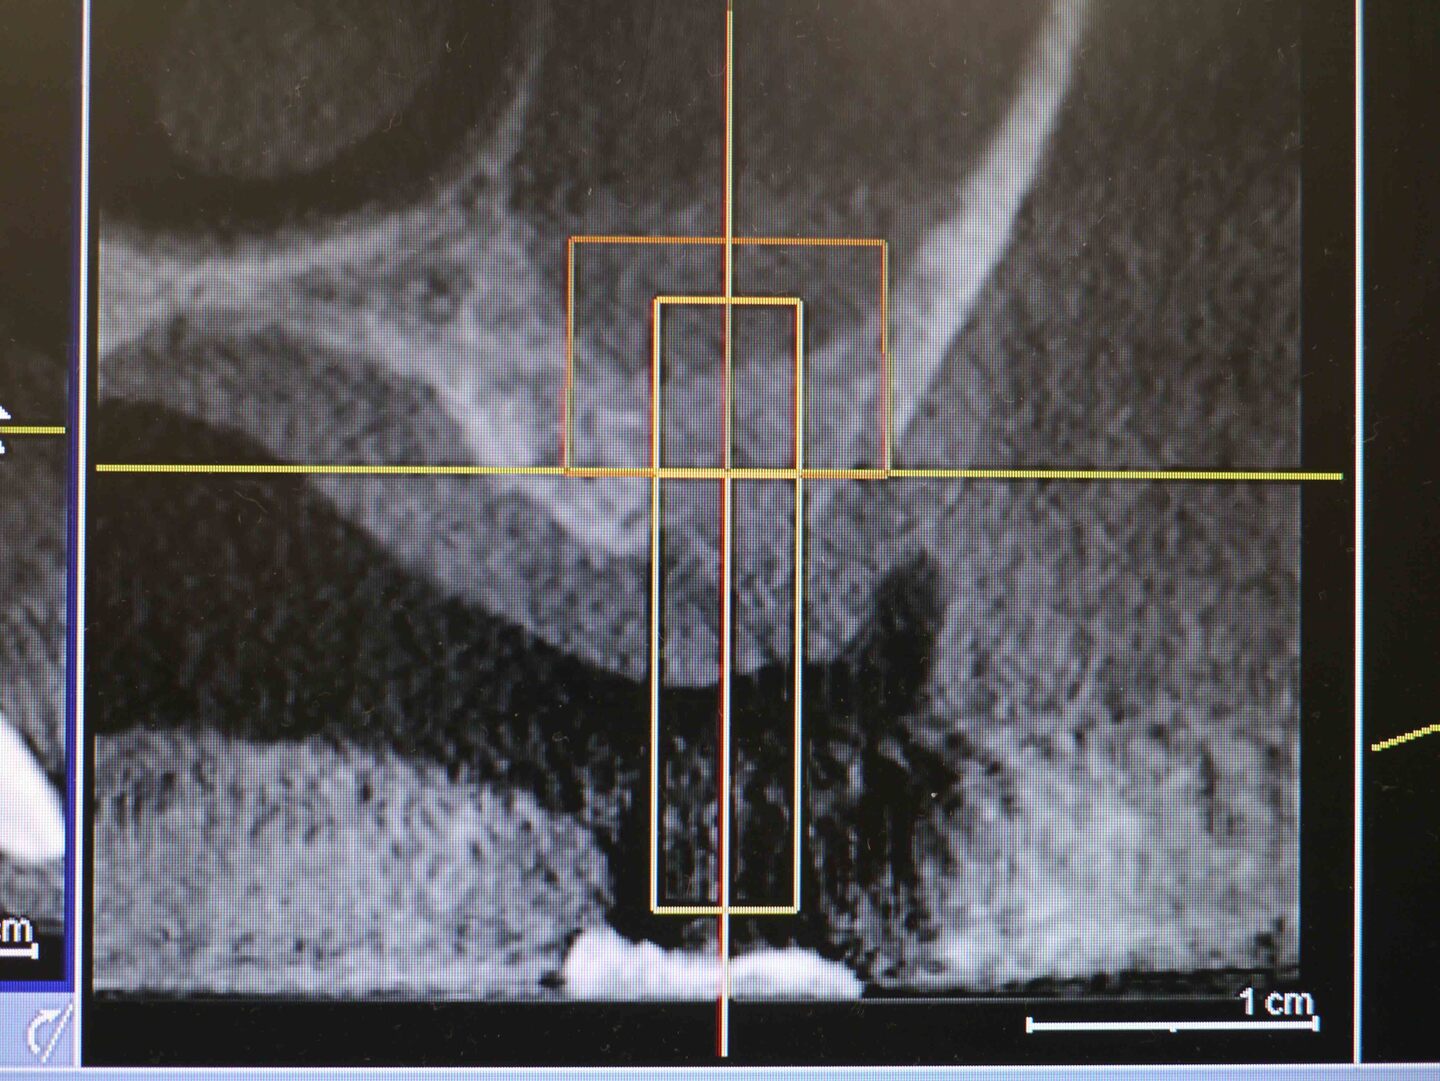

CT画像3

右上6番埋入予定の骨を後側から見たCT